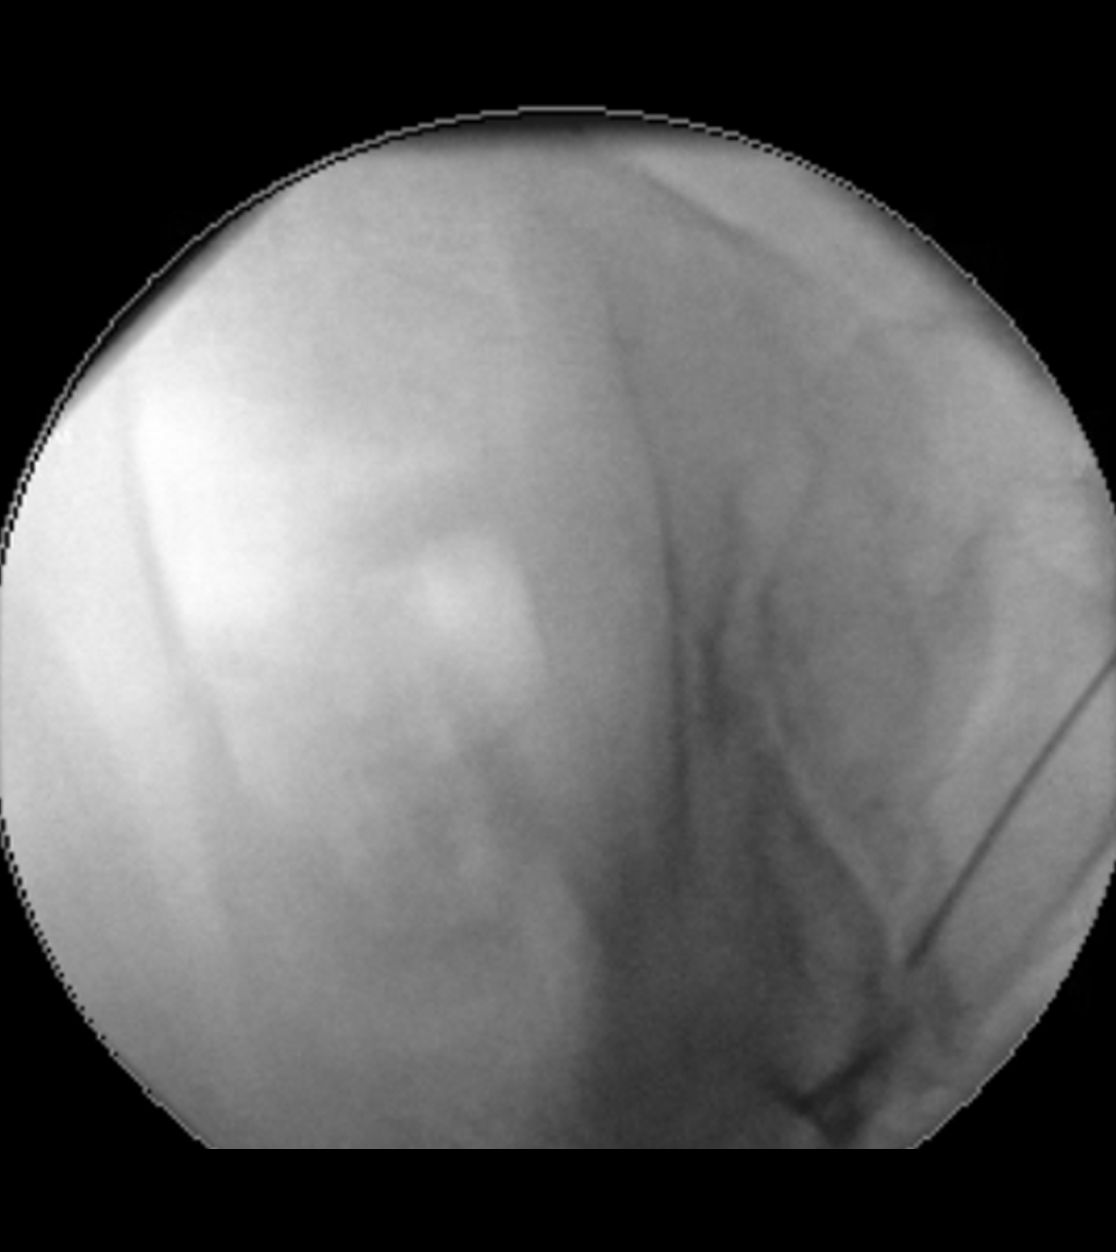

Sollte bei einer Trigeminusneuralgie eine mikrovaskuläre Dekompression nicht infrage kommen, so kann als minimalinvasives Verfahren eine „Verödung“ des Ganglion Gasseri zu einer Schmerzlinderung führen. Hierbei wird unter Röntgenkontrolle eine dünne Nadelelektrode in das Ganglion Gasseri geschoben und mit gezielten Wärmestrahlen eine selektive Vernarbung der Nervenfasern vorgenommen, die für die Schmerzübertragung verantwortlich sind. In einigen Fällen ist im Verlauf bei einer erneuten Zunahme der Beschwerden eine Wiederholung der Prozedur notwendig.

Röntgen-gestützte Infiltrationen stellen eine präzise und schonende Methode zur Behandlung von Rücken- und Gelenkschmerzen dar. Durch den Einsatz von Röntgenbildwandlern wird die genaue Position der Nadel während des Eingriffs sichtbar gemacht, wodurch eine präzise und zielgerichtete Behandlung möglich ist. Zielgebiete der Infiltration sind hierbei die sog. Facettengelenke oder das Ileosakralgelenk (ISG). Wenn die infiltrative Methode nicht ausreicht bzw. die Schmerzlinderung nur kurz anhält, setzen wir auch Facettenthermokoagulationen ein, bei denen durch gezielte Wärmeanwendungen an den betroffenen Nerven die Schmerzübertragung blockiert wird.

Infiltration von Facettengelenken

Infiltration eines Ileosakralgelenks